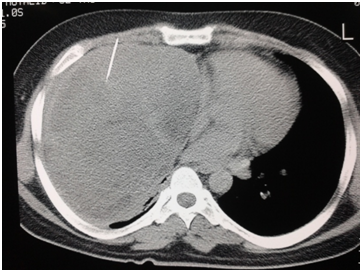

Figure 3 CT scan looks to be a complex hydrated cyst in posterobasal segment of right lower lobe-preoperatively found postero mediastinal cystic mass-histopathological examination showed schawannoma with cystic degeneration.